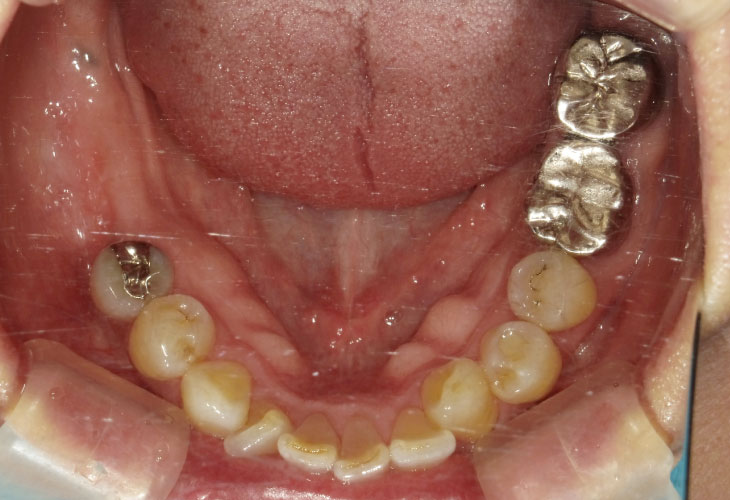

インプラント埋入(左下5・6,右下5・6,左上4・6) サイナスリフト(左上4・6) ジルコニアBr(右上6−左上3) E …続きを見る